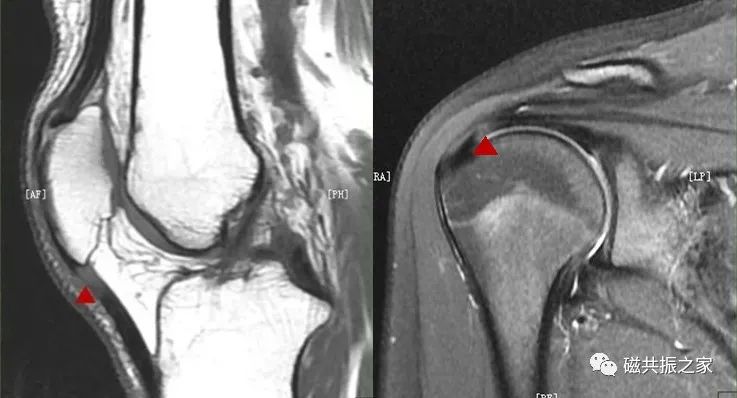

如上图△,图像中三角区域类型水肿信号的表现,其很容易被误诊;重新摆位后下图▽。

图像中局部区域的“水肿”信号消失。实践告诉我们,在四肢关节的扫描中,绝大多数的伪影都是由于摆位不合理造成的。

图△,这类伪影在四肢关节的扫描中并不少见。如不能正确地识别该类伪影,其很容易被误诊为水肿信号。在四肢关节的扫描中正确认识相应的伪影 ,是获得优异图像质量的关键。同时对相应伪影的正确认识,可以有效避免漏误诊的发生。

如魔角效应可出现在任何权重的MRI图像上,以短TE序列最为明显,如T1WI、PDWI图像上。常见于四肢关节的肌腱组织图像上,当在实际扫描中技师遇到该伪影时应知道如何去改善它,诊断医师遇到该伪影时应能正确识别它。